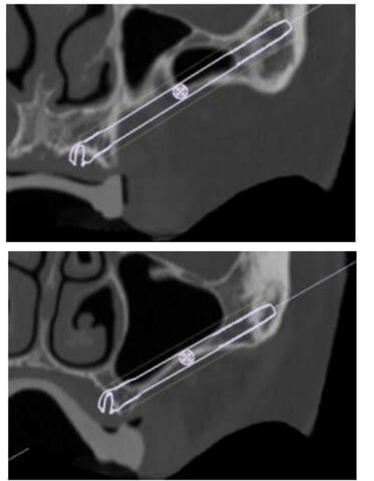

Realizamos CT helicoidal y con FOV ampliado, imprescindible para el diseño de las guías.

Planificamos cuidadosamente la colocación de los implantes teniendo en cuenta, tanto la anatomía maxilofacial como la de la futura prótesis

Planificación 3D personalizada

Se planifica rehabilitación completa con 4 implantes Zygoma.

Planificación 3D y confección de férulas quirúrgicas para abordaje guiado.

Se colocan 4 implantes Zygoma según planificación 3D guiada bajo sedación IV, Carga inmediata a las 24 horas.